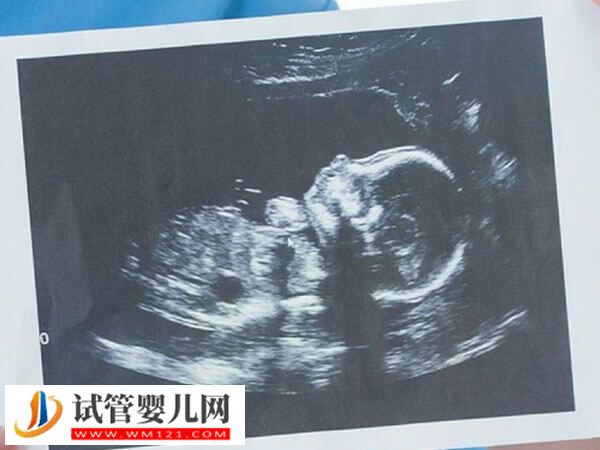

在上海集愛(ài)醫(yī)院做試管的家庭有很多,大部分家庭在就醫(yī)前,都對(duì)試管嬰兒流程有疑問(wèn),其實(shí)集愛(ài)試管的步驟還是比較復(fù)雜的,養(yǎng)囊就是其中必備的流程,目的是增加胚胎移植后著床的概率。

- 6. 養(yǎng)囊:胚胎培養(yǎng)3天后,進(jìn)入養(yǎng)囊階段,有利于移植后的胚胎著床率的提升;

- 7. 囊胚移植:將胚胎移植到女性體內(nèi),移植數(shù)量取決于患者的年齡與胚胎質(zhì)量;